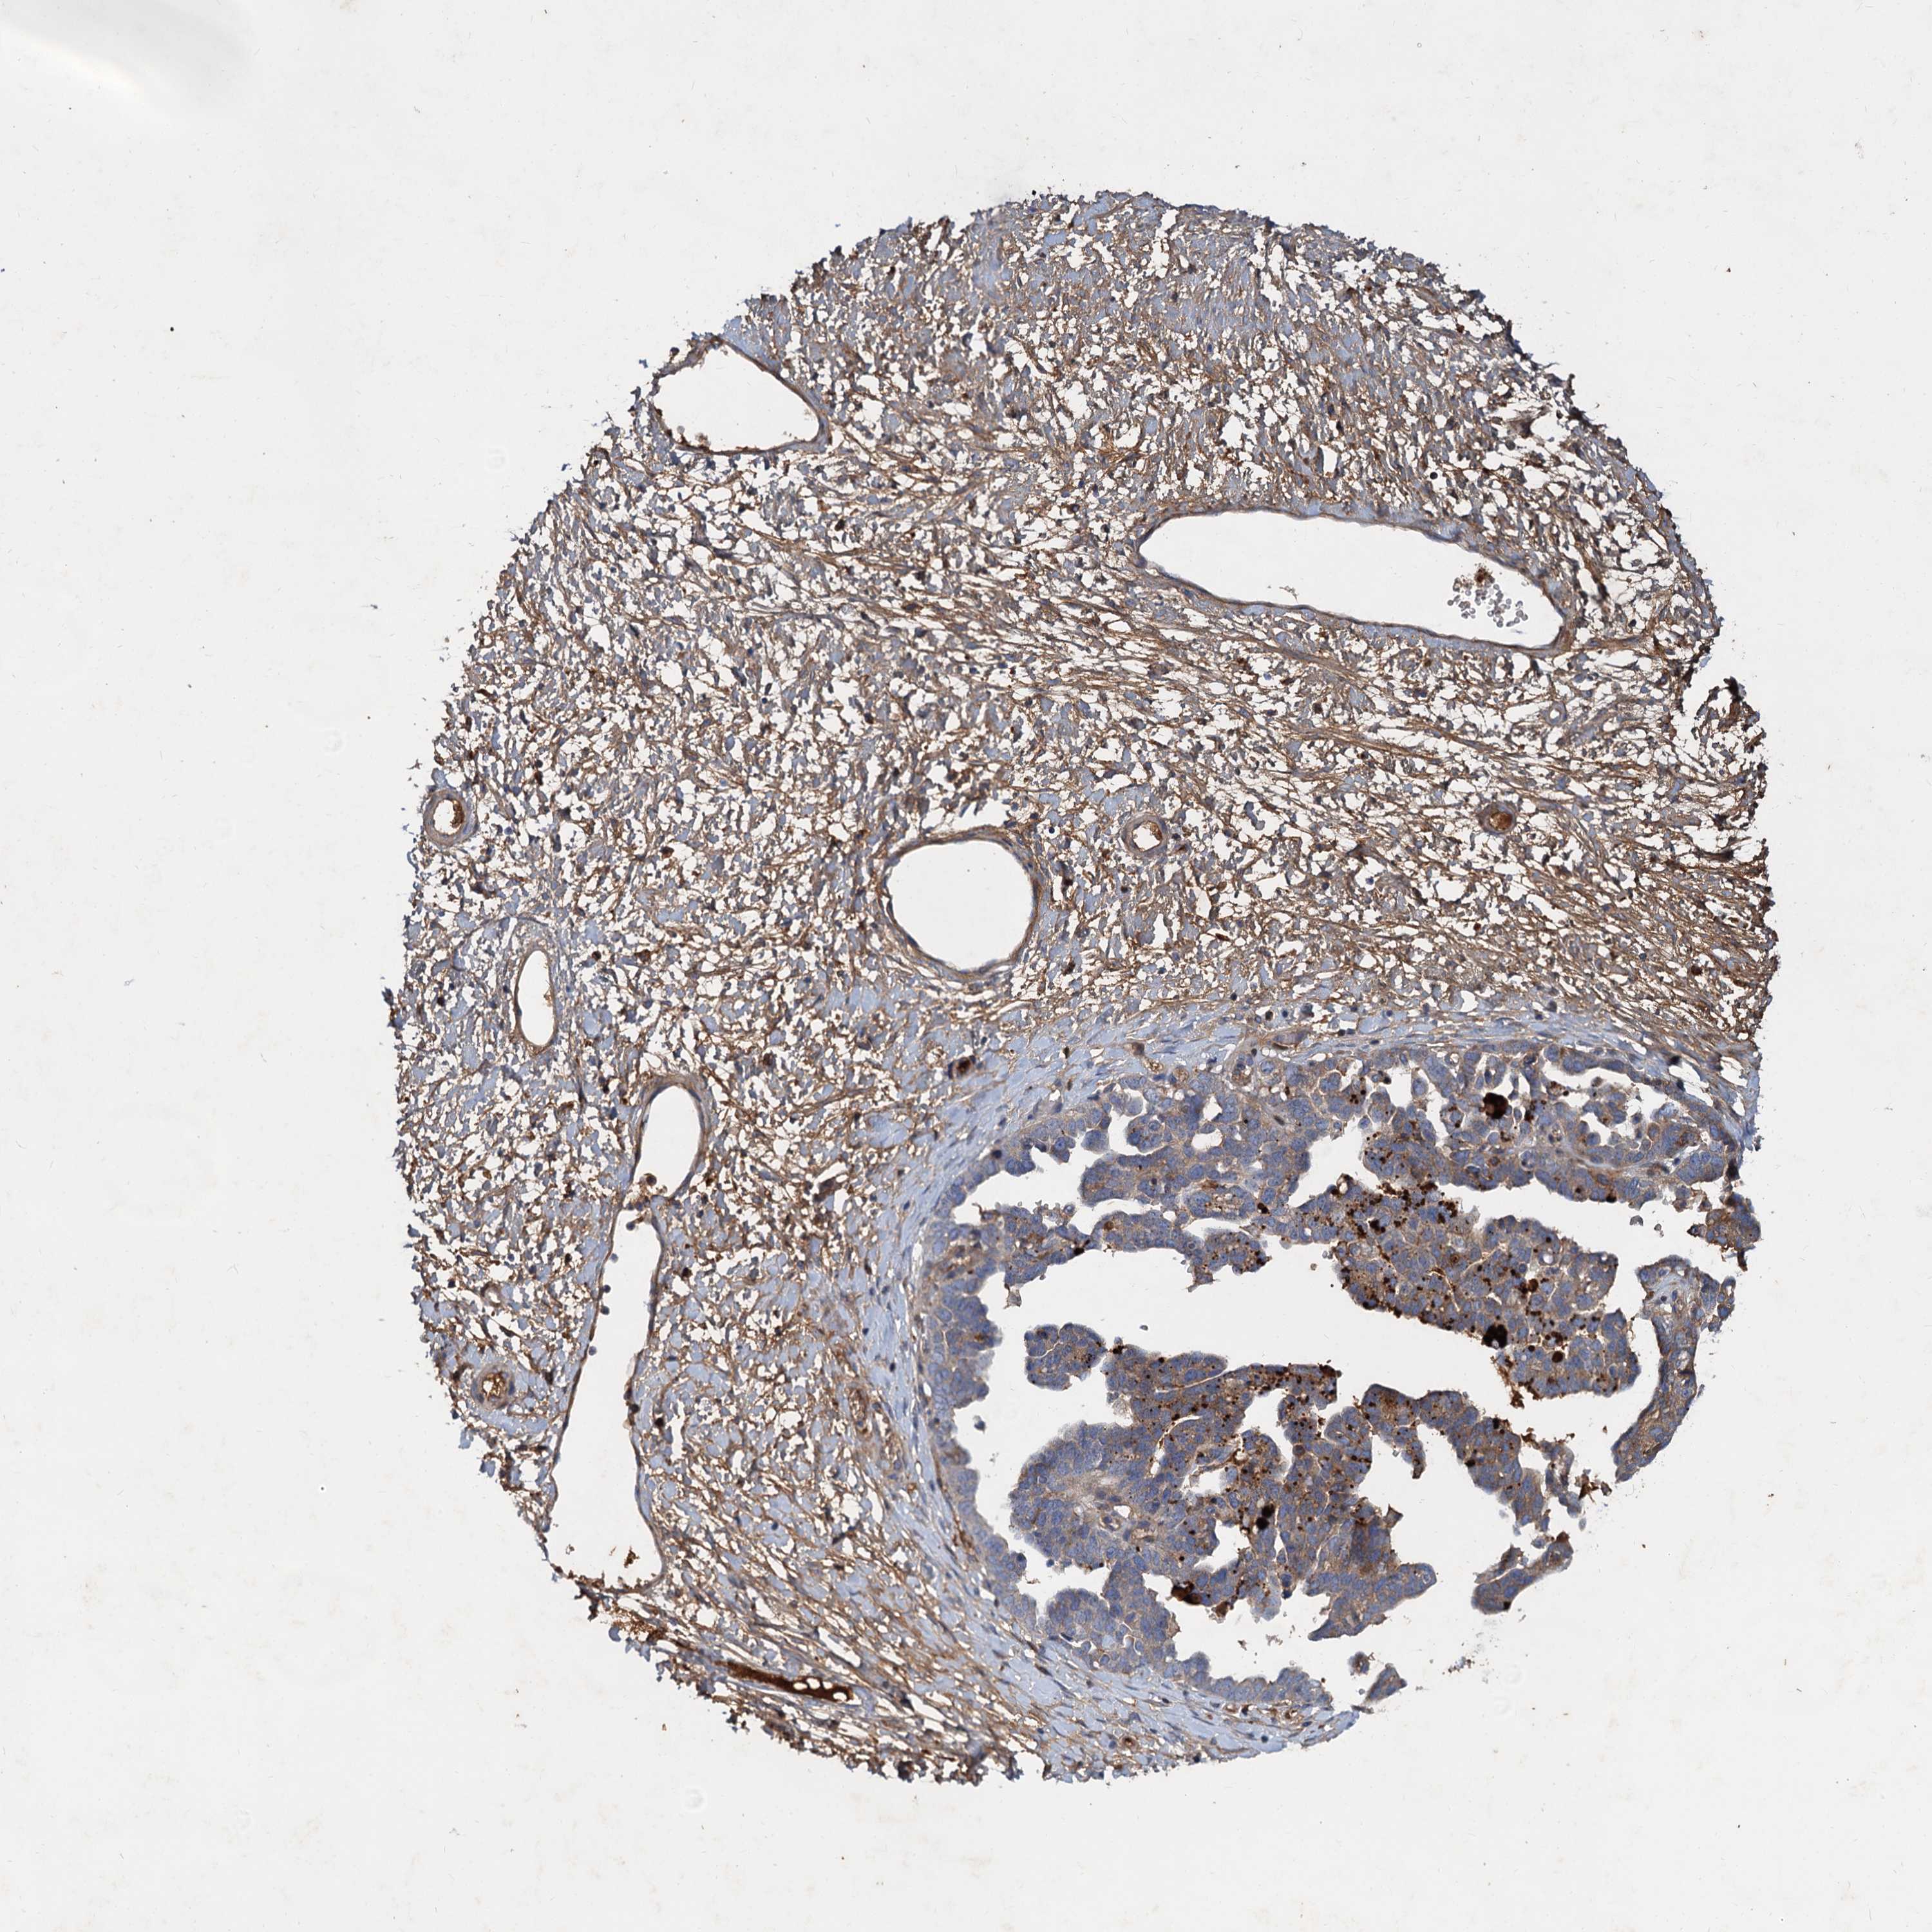

OVARIAN CANCER - Protein expressioni

A mouse-over function shows sample information and annotation data. Click on an image to view it in a full screen mode. Samples can be filtered based on level of antibody staining by selecting one or several of the following categories: high, medium, low and not detected. The assay and annotation is described here.

Note that samples used for immunohistochemistry by the Human Protein Atlas do not correspond to samples in the TCGA dataset.

Antibody stainingi

Antibody staining in the annotated cell types in the current human tissue is reported as not detected, low, medium, or high, based on conventional immunohistochemistry profiling in selected tissues. This score is based on the combination of the staining intensity and fraction of stained cells.

Each image is clickable and will lead to virtual microscopy that enables deeper exploration of all samples and also displays staining intensity scores, fraction scores and subcellular localization as well as patient and tissue information for each sample.

Antibody HPA035827

Staining

High

Medium

Low

Not detected

Intensity

Strong

Moderate

Weak

Negative

Quantity

>75%

75%-25%

<25%

None

Location

Nuclear

Cytoplasmic/membranous

Cytoplasmic/membranous,nuclear

Cystadenocarcinoma, serous, NOS

Carcinoma, endometroid

Cystadenocarcinoma, mucinous, NOS

Carcinoma, NOS